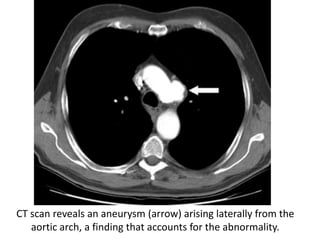

Posteroanterior chest radiograph demonstrates the AP

window with a convex border (arrow)

CT scan reveals an aneurysm (arrow) arising laterally from the

aortic arch, a finding that accounts for the abnormality.